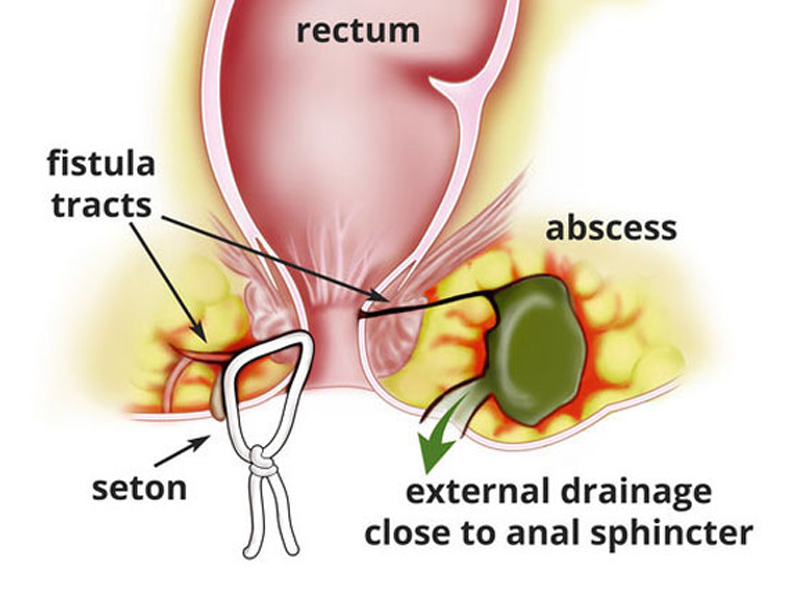

Fistula

The anus is the external opening through which feces are expelled from the body. Just inside the anus are a number of small glands. If one of these..